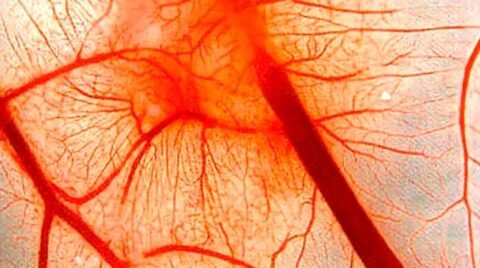

Капилляры в глазу человека

Если сложить длины всех капилляров, то получится путь равный ста тысячам километров, потому что их количество у среднестатистического человека равно десяткам миллиардов. Самые мелкие сосуды подразделяют на несколько видов (таблица), они играют разные роли в человеческом организме.